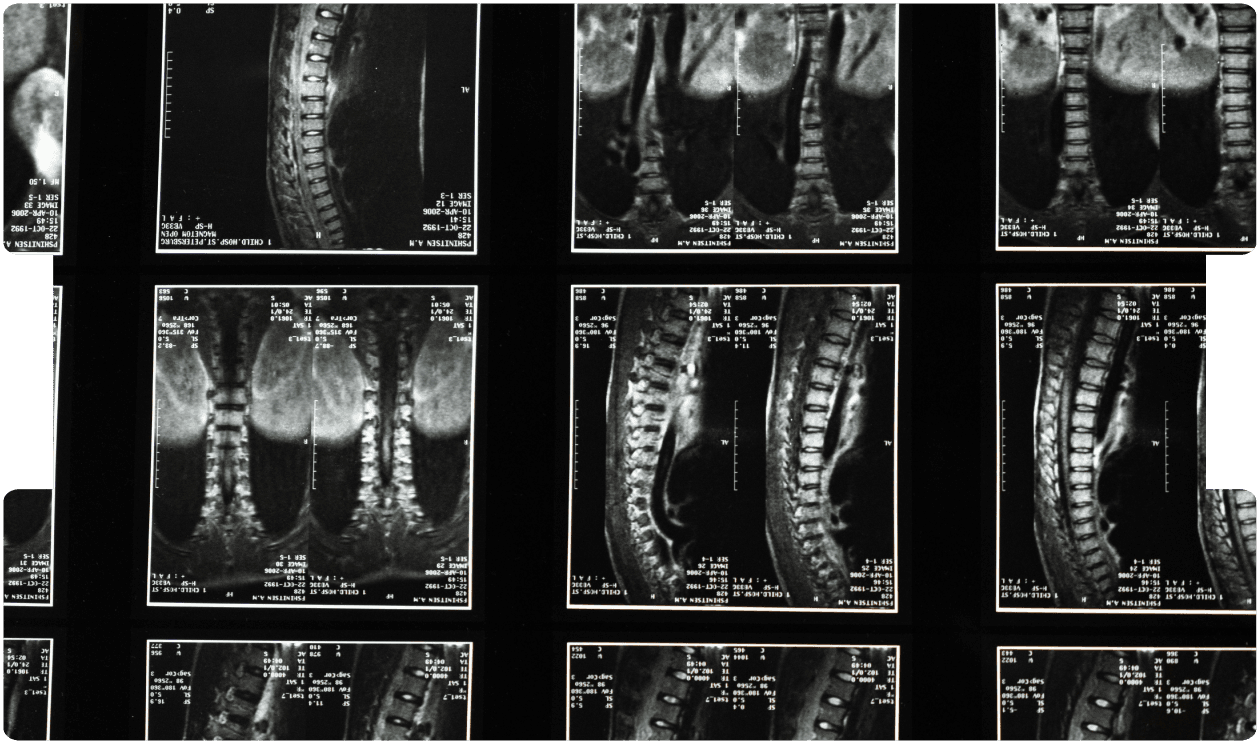

Medicolegal Assessment of Spinal Infection: Diagnosis, Treatment, Outcome and a Medicolegal Experience.

- Spinal Infection